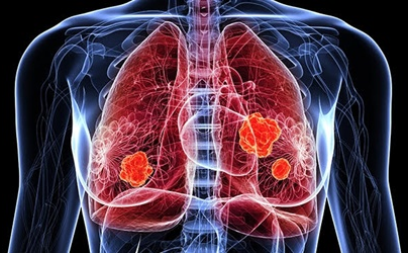

7. 폐암의 초기 증상 - 뼈 통증

암세포는 뼈에도 영향을 미칩니다 . 특히 폐에 가까운 갈비뼈에 암이 퍼지는 경우 가 많습니다 . 따라서 갈비뼈 부분의 통증과 흉통을 호소하는 경우가 많습니다 . 암이 많이 퍼진 경우는 어깨와 상반신 전체을 통해서 통증을 호소 할 수도 있습니다 . 폐암으로 인한 통증 뿐만 아니라 뼈가 약해져 외부 충격이 없는데도 골절이 나타나거나 합병증이 발생할 수 있습니다 .